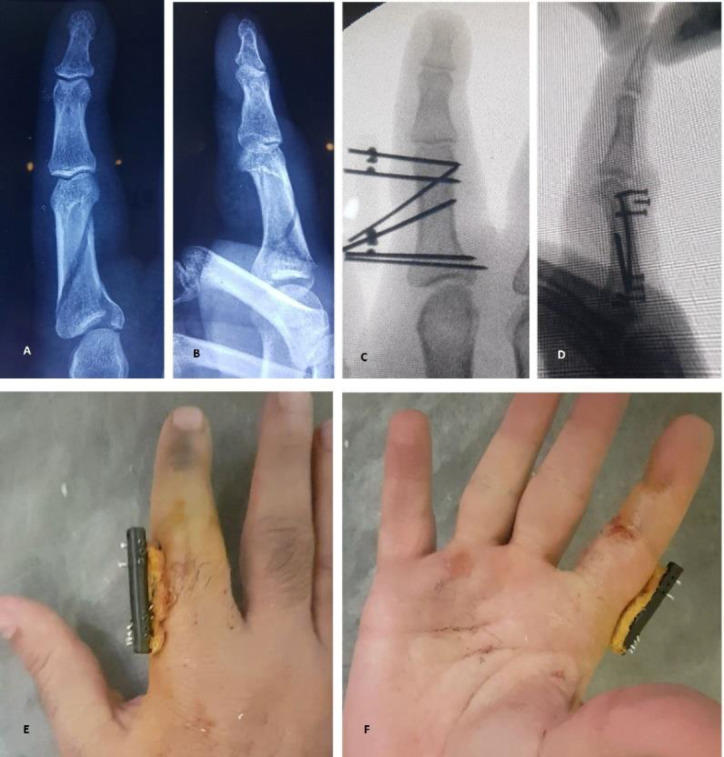

Objectives: Hand fracture is one of the most common fractures in the skeletal system. The present study aimed to introduce a newly designed external fixator and assess the results of treatment of patients with unstable and complex fractures of the proximal and middle phalanges of the fingers with two treatment methods: "fixation with percutaneous pins (PCP) + splint" and "fixation with mini external fixator.

Methods: In this prospective cohort study, patients with acute unstable and complex fractures of the proximal and middle phalanges of the second to fifth fingers were treated with two treatment methods, including "fixation with PCP + splint" and "the use of mini external fixator." At the final follow-up visit, union, pain, function, finger range of motion (ROM), and possible complications were considered.

Results: Among 52 patients included in the study, 33 cases were treated with a mini external fixator, and 19 patients underwent fixation with PCP and splint. All patients in both groups had a union, and none of them complained of pain during the final visit. Functional outcomes were good, and there was no statistically significant difference between the two groups. The mini external fixator group had a significantly greater finger ROM (P=0.012), with a lower number of physiotherapy sessions (P=0.018). Moreover, patients returned to work more promptly (P=0.012).

Conclusion: The treatment of unstable finger fractures with a mini external fixator had three advantages: the possibility of early initiation of finger movement and improvement of finger ROM, the need for fewer physical therapy sessions, and early return to work. It can be an effective treatment option for unstable and complex finger fractures.